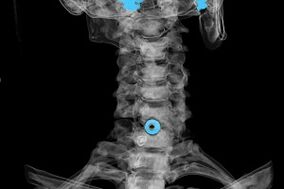

La diagnosi viene stabilita sulla base dei sintomi caratteristici, nonché utilizzando:

- Raggi X. Il metodo è inefficace, soprattutto nelle ultime fasi dello sviluppo dell'osteocondrosi.

- MRI (risonanza magnetica) del rachide cervicale. Un metodo che permette di vedere le strutture ossee, le ernie dei dischi intervertebrali, la loro dimensione e direzione di sviluppo.

- Tomografia computerizzata. Una soluzione meno efficace della risonanza magnetica, poiché la presenza e la dimensione delle ernie sono difficili da determinare.